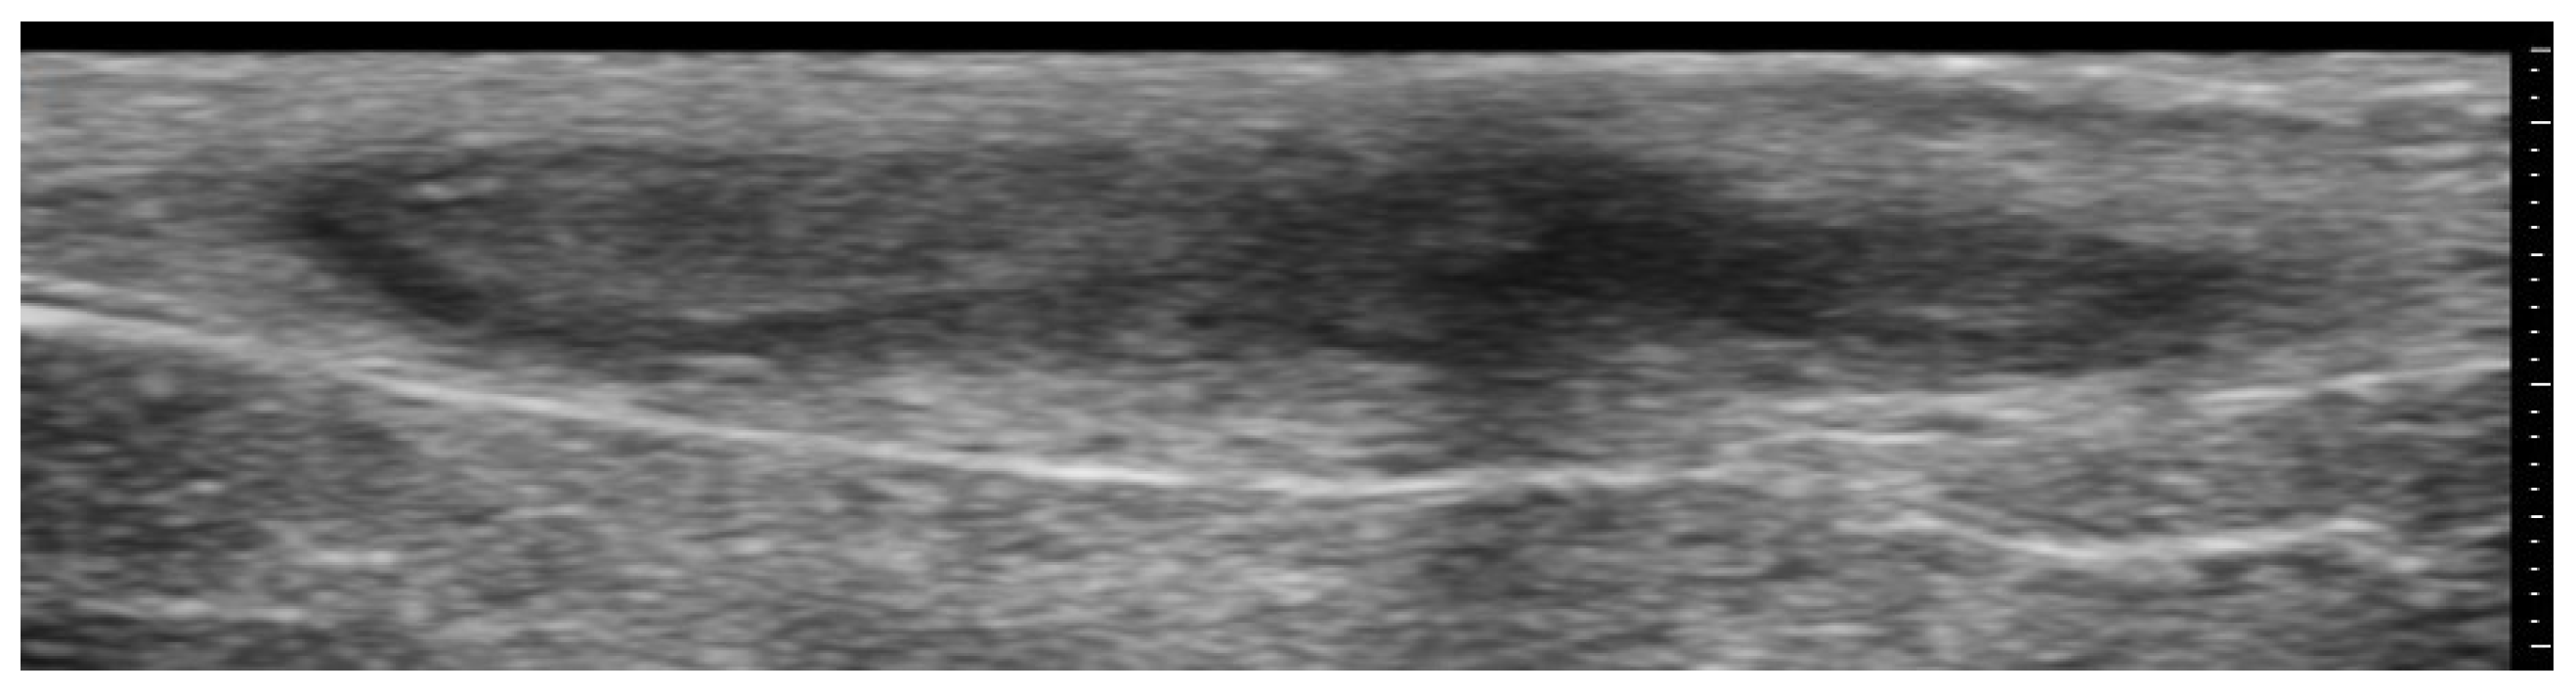

- Yazdanparast, T.; Mohseni, A.; Dehghan, K.S.; Delavar, S.; Firooz, A. High-frequency ultrasound evaluation of morphea: Retrospective analytical study. Ski. Res. Technol. 2024, 30, e13818. [Google Scholar] [CrossRef] [PubMed]